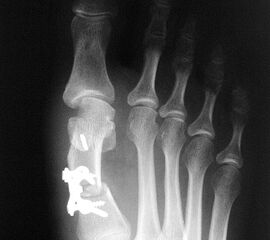

Beim Follow up nach 6 Monaten zeigte sich eine Korrektur des ersten Intermetatarsalwinkels (IMW) um durchschnittlich 9° (Range 4-15°) auf Normwerte (6,8° SD 1,3) (Abb. 21).

Gutes postoperatives Ergebnis mit physiologischem Intermetatarsale I-II Winkel nach open wedge Osteotomie.

Abbildung 21

In zwei Fällen kam es intraoperativ zu einem Bruch der lateralen Kortikalis. In einem Fall konnte durch die winkelstabile Platte eine ausreichende Stabilität erzielt werden, in dem anderen Fall wurde zusätzlich ein perkutaner Kirschnerdraht eingebracht, der nach 6 Wochen entfernt wurde. Eine stabile knöcherne Konsolidierung der Osteotomie ohne Korrekturverlust konnte in beiden Fällen erreicht werden. Die Analyse der Röntgenaufnahmen ergab eine Verlängerung des Os metatarsale I von durchschnittlich 1,8 mm (Range 1-4 mm).